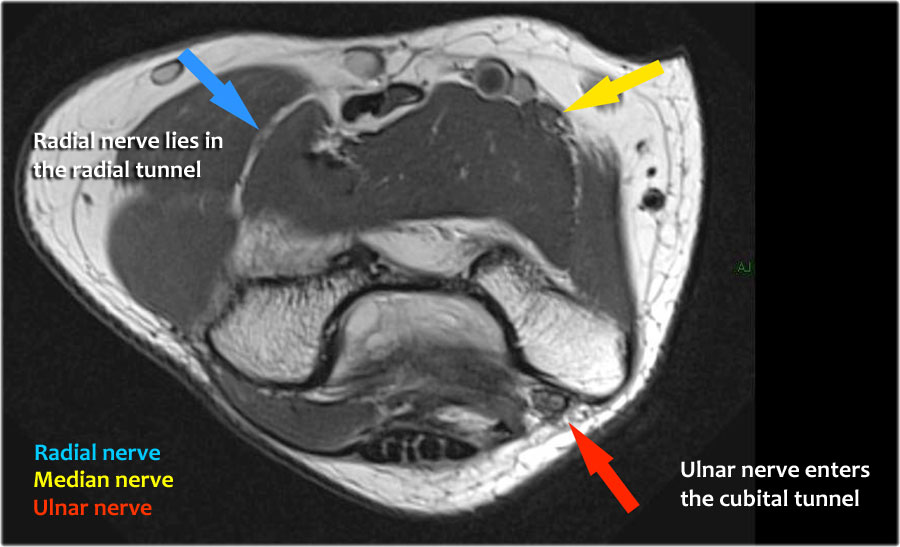

Scroll through the images.

Ulnar nerve

Ở đây chúng ta thấy dây thần kinh trụ nằm trong ống trụ.

Bó sau của dây chằng bên trụ tạo thành sàn của ống, trong khi mạc hãm tạo thành trần của ống.

Radial nerve

Dây thần kinh quay có thể được xác định rõ nhất ở mức chỏm xương quay, nơi có thể quan sát thấy các nhánh nông và nhánh sâu trong ống xương quay (mũi tên).

This is a very consistent place to find the radial nerve.